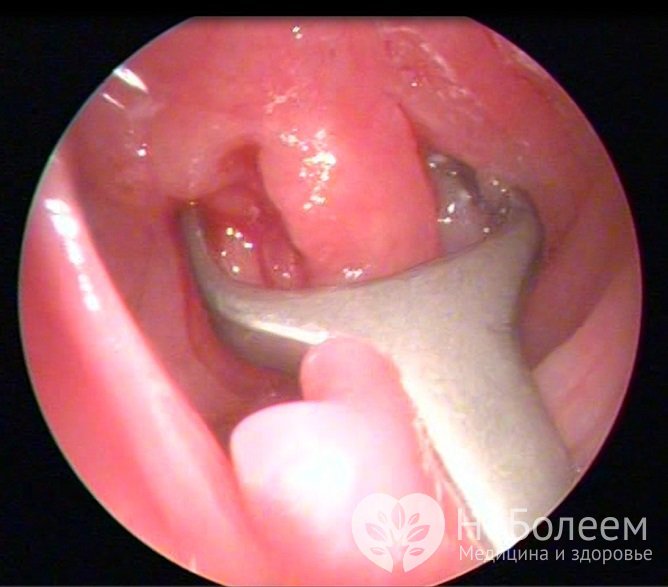

Хирургическое удаление аденоидов производится специальным инструментом – аденотомомВ классической операции для удаления аденоидов используется кольцевидный нож – аденотом. После удаления аденоидной ткани развивается обильное кровотечение, которое обычно быстро прекращается. Если этого не происходит, необходимо осмотреть носоглотку, где обнаруживаются обрывки тканей, после удаления которых кровь останавливается. Усовершенствованной модификацией этого метода является эндоскопическое иссечение аденоидов, обеспечивающее хороший обзор операционного поля и большую точность вмешательства, а значит, и меньшие риски.